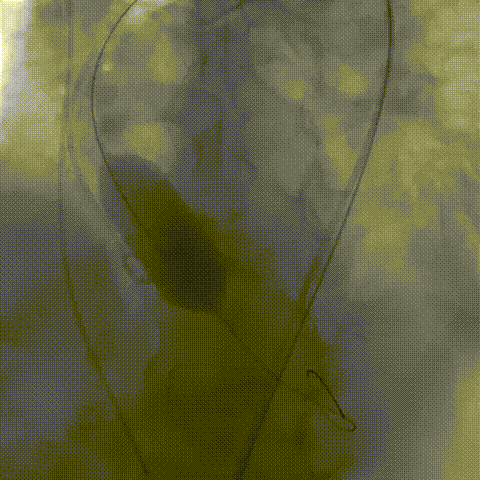

初次释放,无冠窦畸形猪尾难以到达窦底,定位带来挑战;释放至工作位,瓣膜(AV29)位置偏低

瓣膜(AV29)完全回收后重新定位释放

瓣膜(AV29)工作位正交体位造影位置良好,左冠显影正常